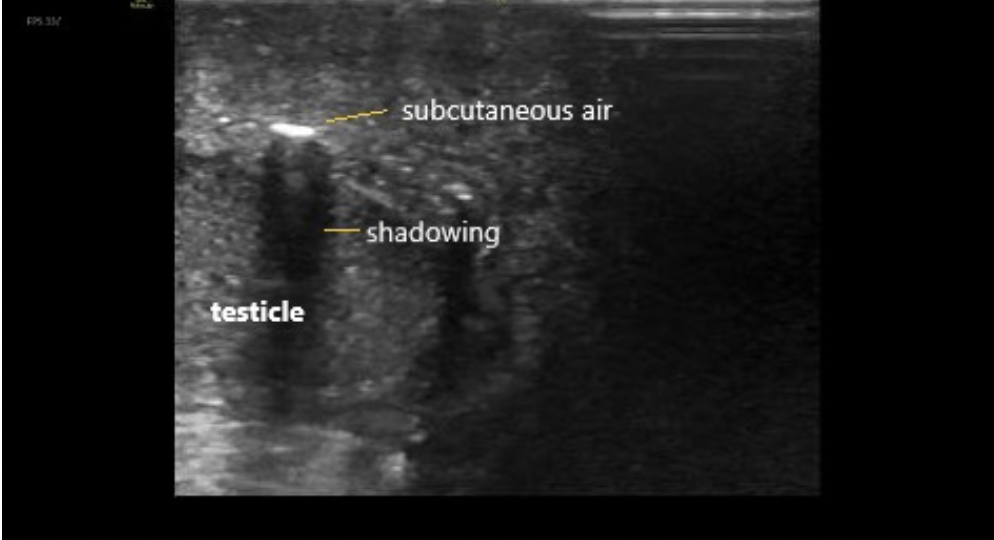

A 60 year-old male with history of poorly controlled diabetes, congestive heart failure, chronic kidney disease, and a prior MI presented as a transfer from an outside hospital for surgical management of suspected necrotizing fasciitis/Fournier’s gangrene. He reported symptoms of diarrhea, nausea, vomiting, and severe pain in the scrotum and perineum for several days. This began after he sustained a small cut to the area. He denied fevers, urinary discharge, respiratory symptoms, chest pain, but did endorse chills and night sweats…